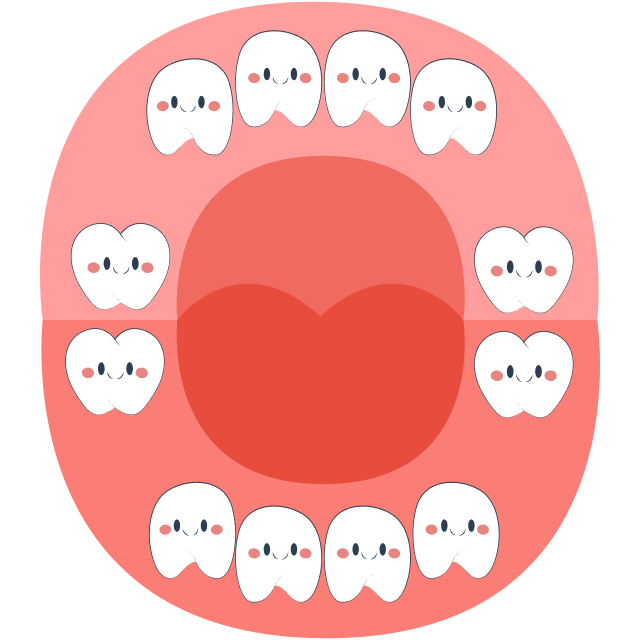

At around 6 years old, children prepare to lose their first tooth, and primary (baby) teeth will gradually be replaced by permanent teeth. The tooth replacement sequence typically begins with the eruption of the first molar (tooth number 6) and ends with the eruption of tooth number 7 around the age of 12.